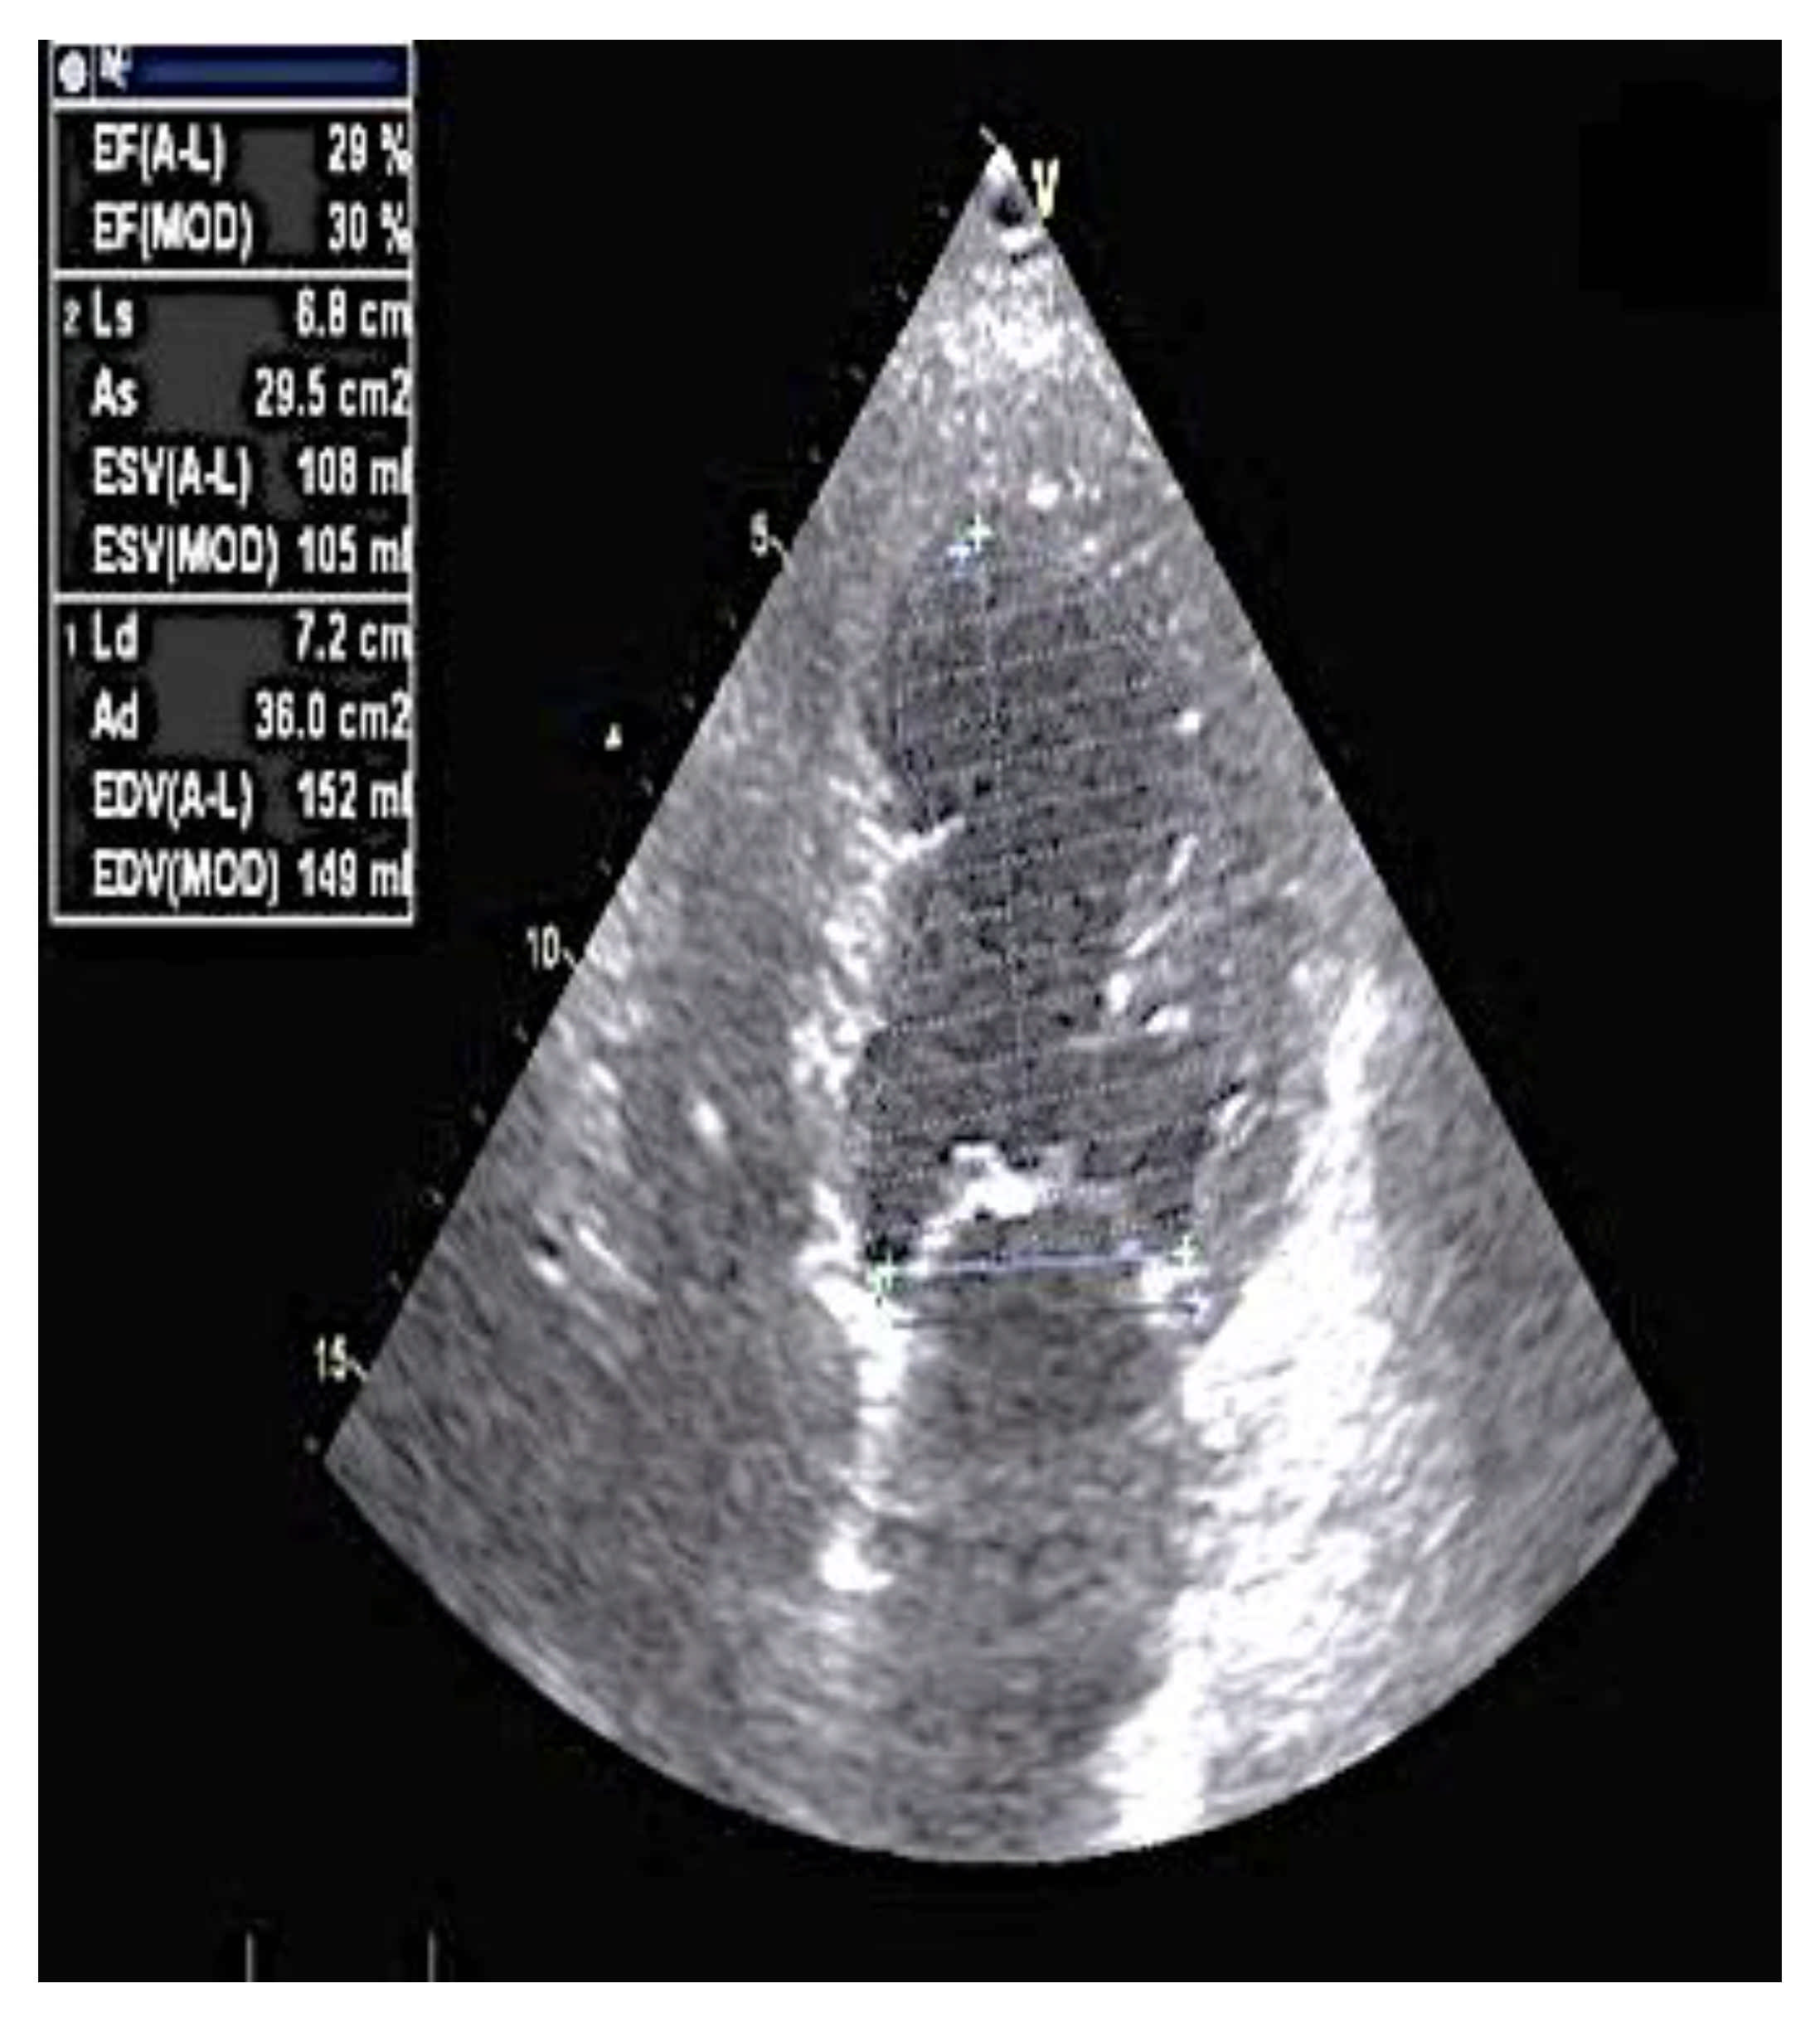

2. Case Report